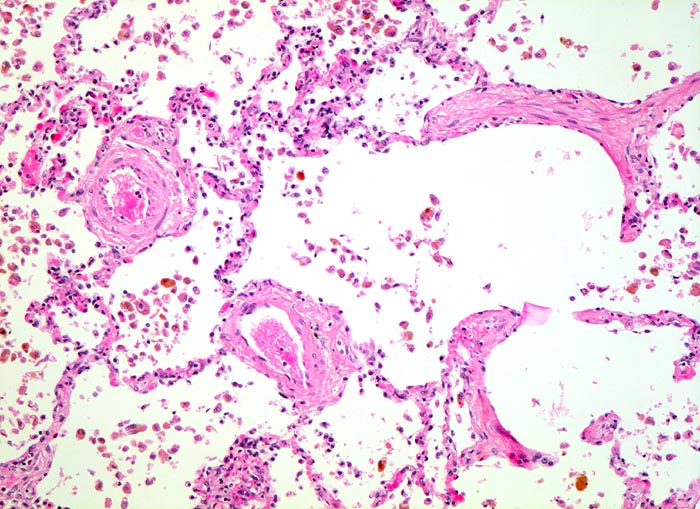

Herzfehlerzellen

vaskulär / Durchblutungsstörung

Siderophagen lassen sich im Sputum nach intraalveolären Blutungen nachweisen. Intraalveoläre Blutungen infolge Linksherzinsuffizienz sind die häufigste Ursache. Andere Ursachen für intraalveoläre Blutungen sind Lungeninfarkte, eine toxische Kapillarschädigung, eine Vaskulitis oder Blutaspiration. Der Nachweis von Erythrozyten im Zytoplasma von Makrophagen spricht für eine frische Blutung. Hämosiderin wird nach 3-5 Tagen mit der Eisenfärbung nachweisbar. Als sicherer Hinweis auf eine ältere Blutung gelten >20% Siderophagen in der BAL.